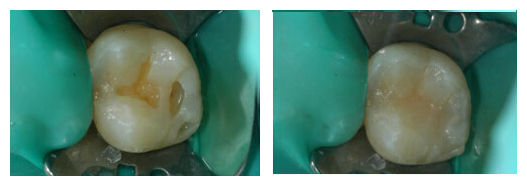

补牙

后还会疼吗?

补牙,又称充填术。目前常用的充填材料(补牙材料)虽对人体无害,但对牙髓有一定的刺激作用,如龋洞太深时用护髓材料护髓,就会因分离出某些物质刺激牙髓而发生疼痛;复合树脂,对牙髓也有刺激作用,这些材料不能直接充填较深的龋洞,必须先用无刺激的材料垫上一层后再选用其他材料充填,否则就会导致充填后疼痛。

牙齿烂了洞后,要尽早去医院补牙。牙齿修补好后使用时间的长短,有多种因素。首先是补牙的时机。病人就诊时牙齿龋坏的程度、部位及牙洞的形状都有很大的关系;其次是补牙的材料。不同的材料与牙洞的粘结性有所不同;最后是补牙前牙洞的处理。具体补牙后能用多久也是因人而异的,保护得当自然使用时间长。